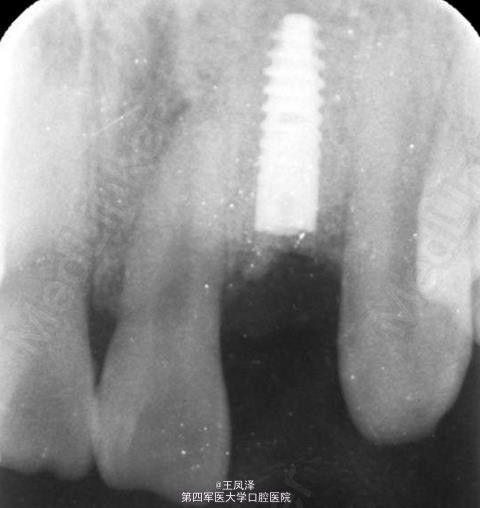

x线检查:22根尖区有阴影。诊断:22牙根纵折伴根尖周炎。

22牙根纵折伴根尖周炎。 治疗计划:1.拔除22. 2.三个月后延期种植22